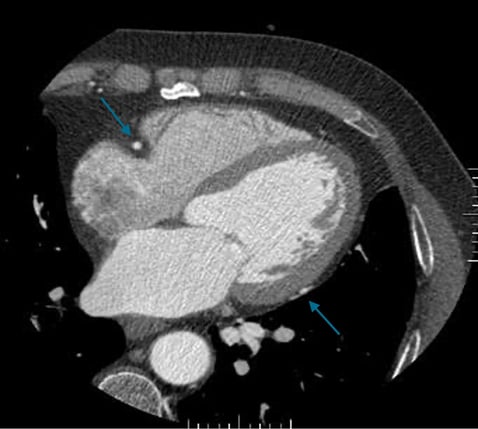

Example of a sufficiently good examination. Good contrast in the coronary arteries. The heart is displayed without steps.

Another example after 3D post-processing (obligatory vessel and volume display): The coronary vessels are clearly and continuously displayed. Image source: Rolf et al. 2023